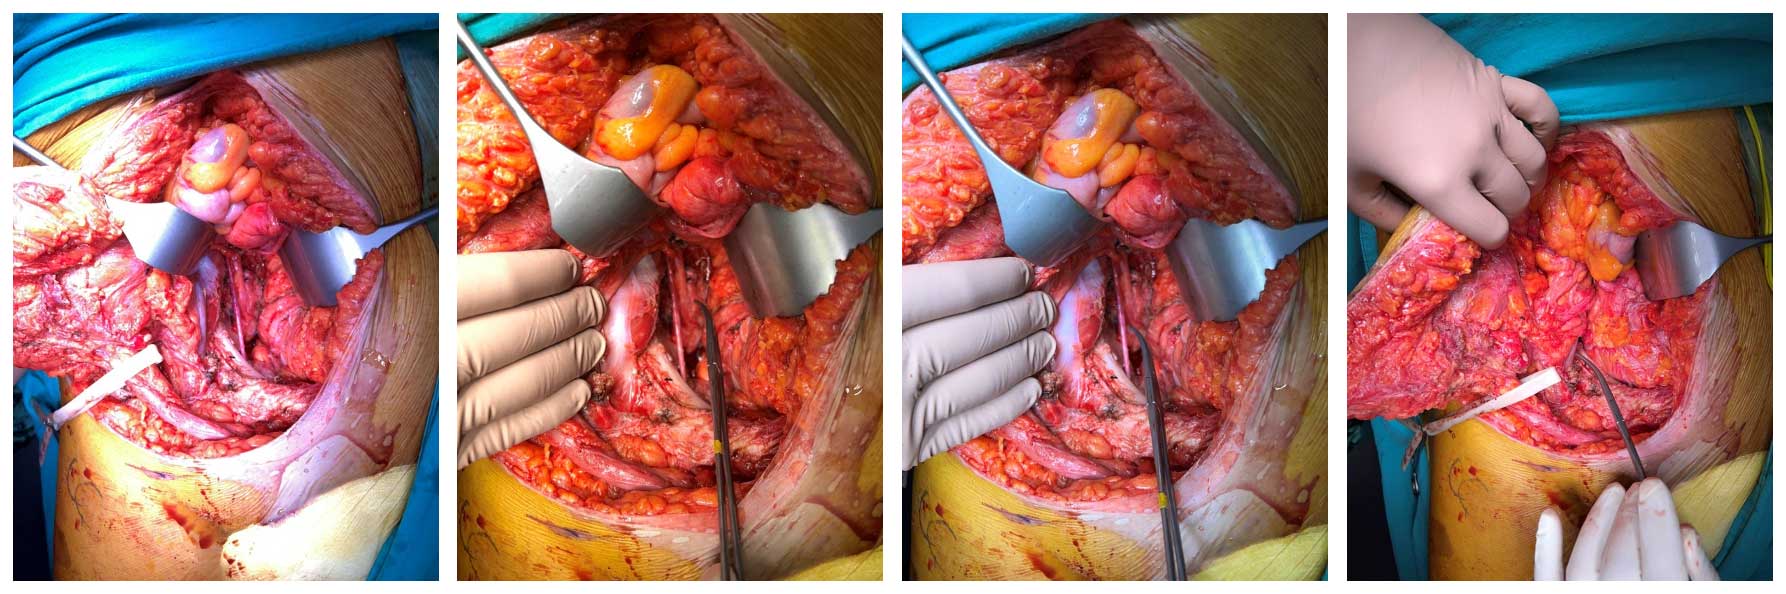

Ameliyat Esnası: İntrapelvik anatomik yapılar görülmekte.

Ameliyat Esnası: Çıkarılan tümör dokusunun klinik görüntüsü.